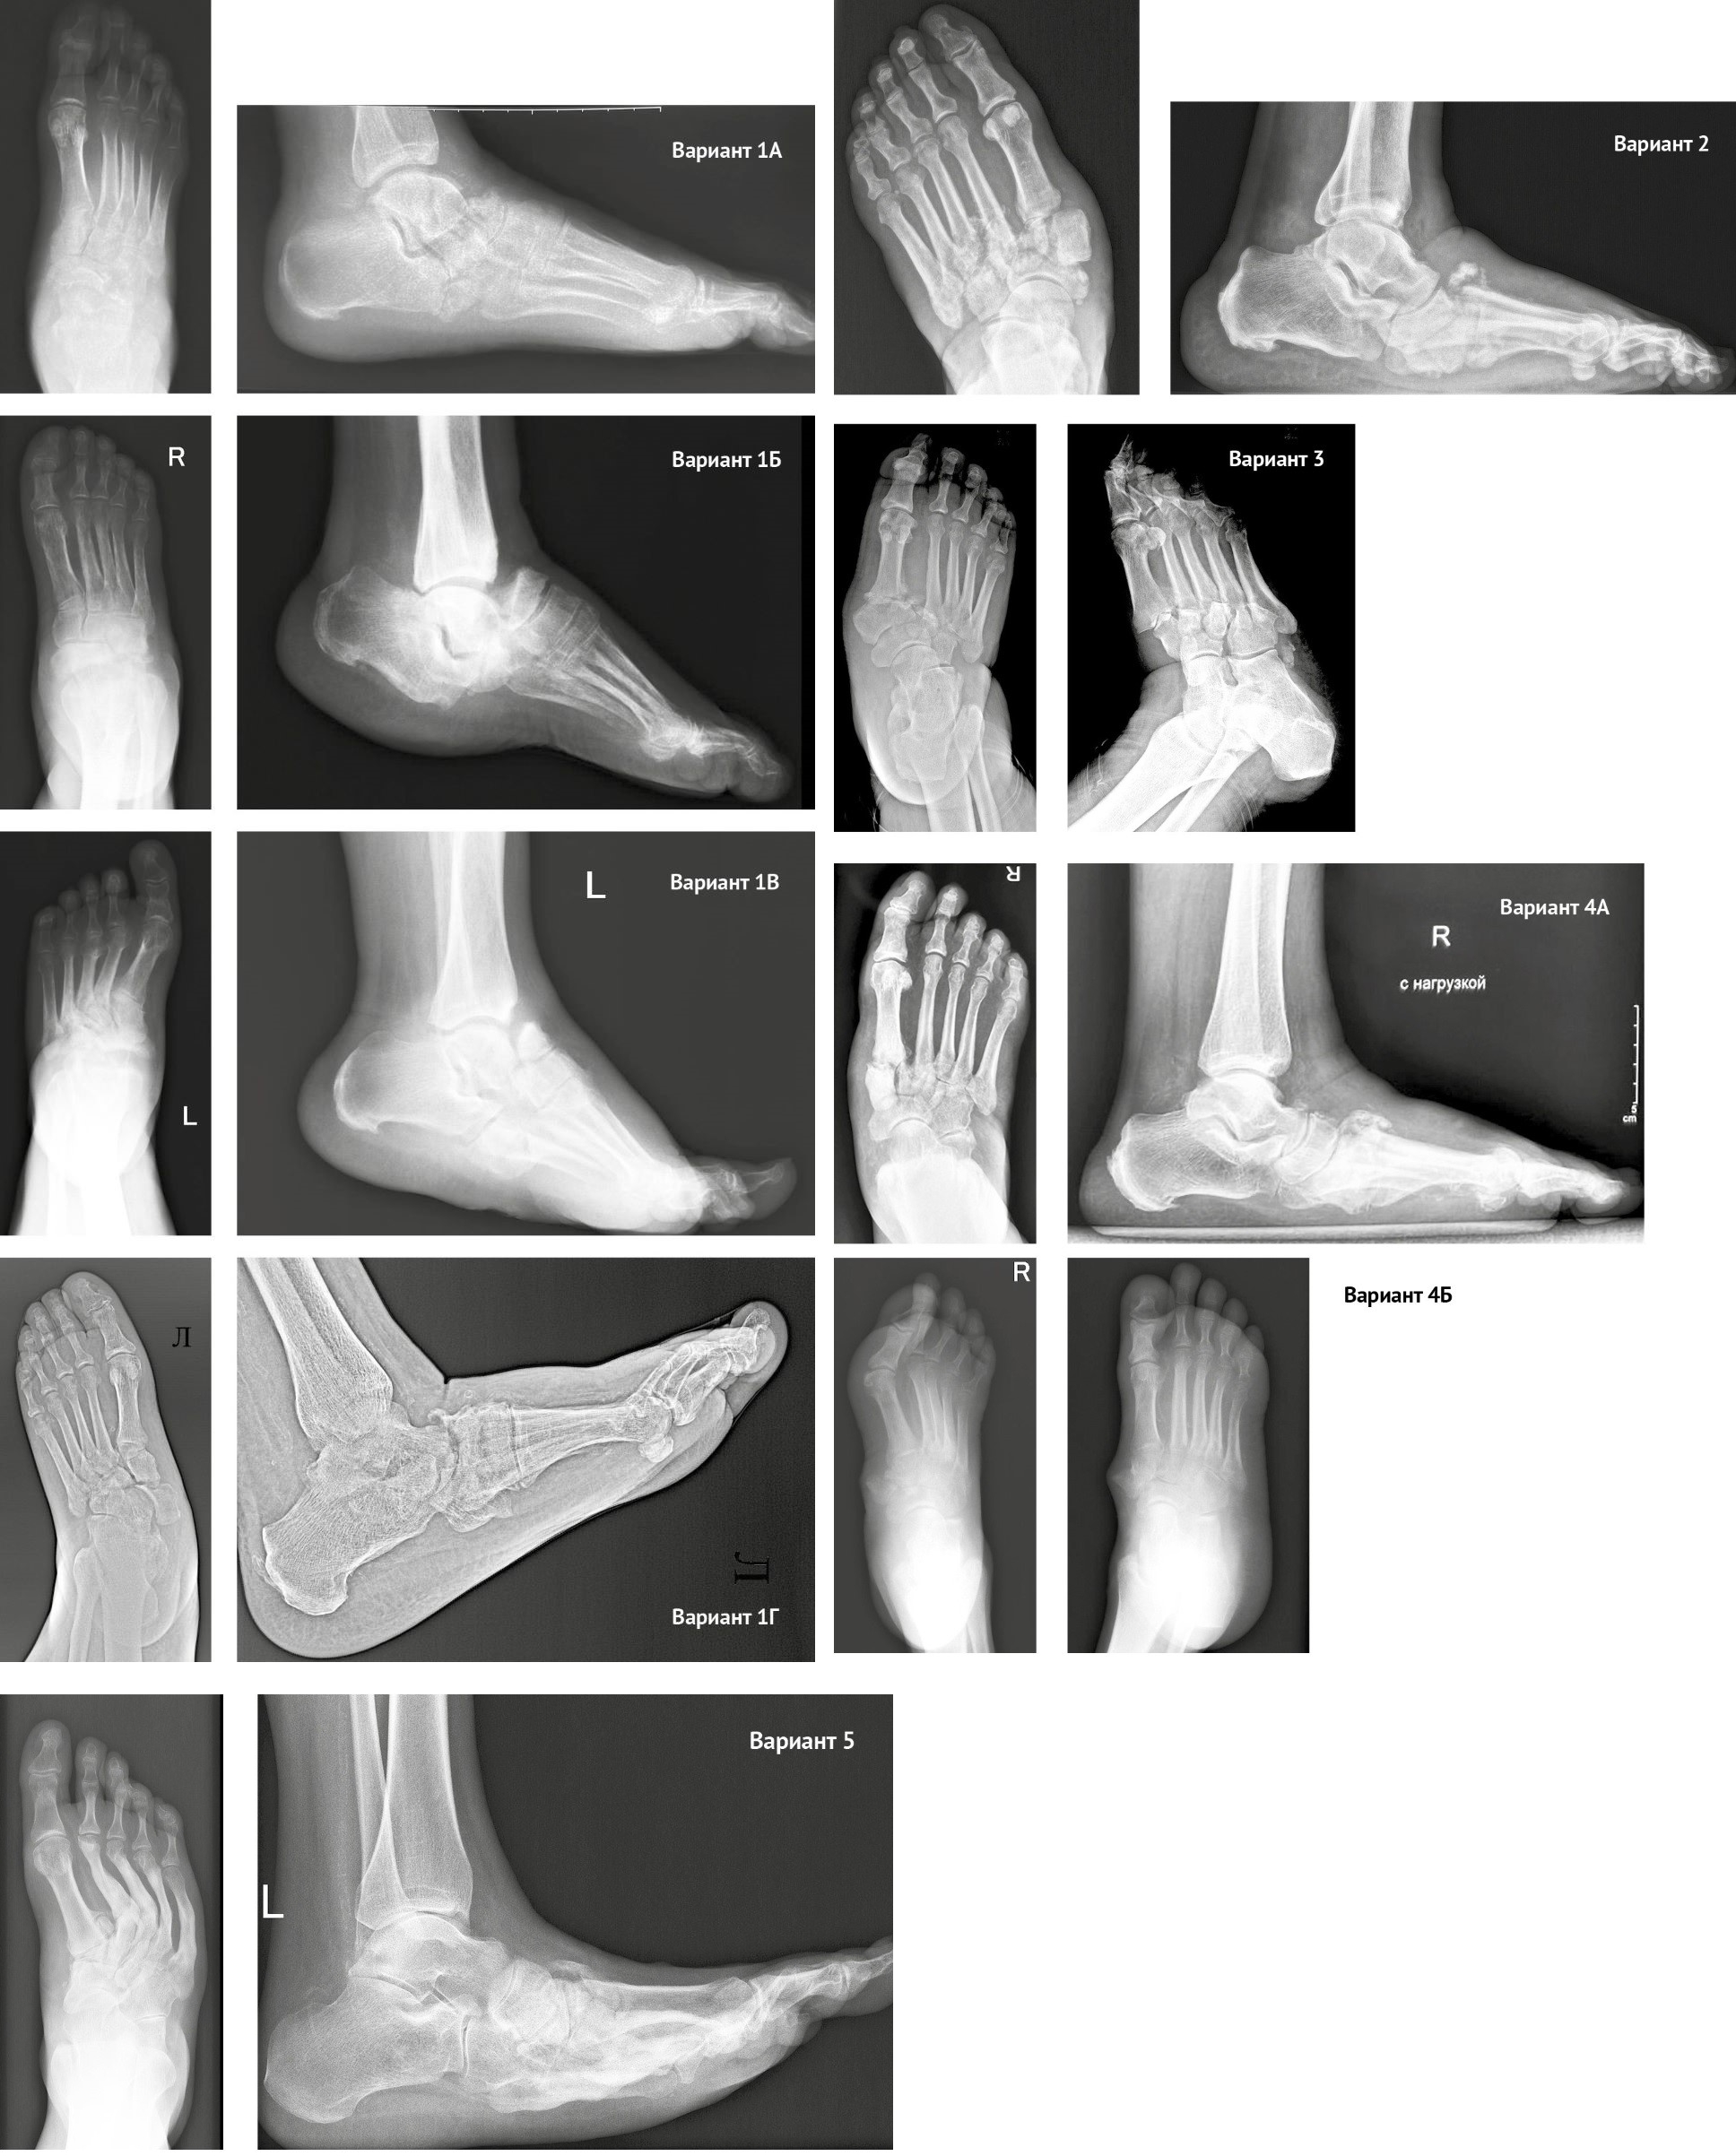

The deformity variants are illustrated in X-rays (Figure 2).

Figure 2. Deformity variants

Variant 1А. Involvement of the navicular bone and talar head with the preservation of the lateral column anatomy. Typical features of this subtype include:

- defect of the talar head and/or navicular bone;

- preservation of an intact lateral column;

- no visually significant foot deformity.

Variant 1B. Simultaneous involvement of the talonavicular and calcaneocuboid joints (dorsal dislocation or subluxation of the navicular and cuboid bones). Typical features of this subtype include:

- dorsal displacement of the midfoot bones (navicular and cuboid) relative to the hindfoot bones (talus and calcaneus);

- preservation of an intact tarsometatarsal (Lisfranc) joint;

- equinus positioning of the talus and calcaneus bones without disruption of the subtalar joint alignment.

Variant 1C. Simultaneous involvement of the talonavicular and tarsometatarsal joints (dorsal dislocation or subluxation of the navicular and cuboid bones). This subtype is characterized by:

- dorsal displacement of the navicular bone along with the midfoot and forefoot bones;

- plantar dislocation of the cuboid bone at the cuboid-metatarsal joint;

- equinus positioning of the hindfoot (talus, calcaneus, and cuboid bones).

Variant 1D. Total displacement of the navicular bone with dislocation at the talonavicular and naviculocuneiform joints. This subtype is characterized by:

- plantar and/or medial dislocation of the navicular bone;

- dorsal dislocation of the medial cuneiform bone;

- dorsolateral displacement of the metatarsal bones;

- plantar displacement of the cuboid bone at the cuboid-metatarsal joint;

- dislocation of the intermediate and lateral cuneiform bones either in plantar direction together with the cuboid bone or dorsally along with the metatarsals;

- supinated positioning of the metatarsal bones;

- equinus positioning of the hindfoot.

Variant 2. Deformity (subluxation, dislocation, or fracture-dislocation) of the naviculocuneiform joint, possibly involving the lateral column at the cuboid-metatarsal joint, with progressive deformity and flattening of the medial column. This subtype is characterized by:

- destruction within the naviculocuneiform joint with preserved anatomical alignment of the Chopart joint;

- possible involvement of the lateral column at the tarsometatarsal joint;

Variant 3. Deformity (subluxation, disloca-tion, or fracture-dislocation) of the Lisfranc joint. This subtype is characterized by:

- subluxation of the metatarsal bones in the Lisfranc joint with valgus positioning and abduction;

- prolapse of the foot with plantar displacement;

- possible destructive changes in the Lisfranc joint;

- development or worsening of pre-existing valgus foot deformity;

- depending on the severity of destruction, possible plantar dislocation of the cuboid bone in the cuboid-metatarsal joint.

Variant 4. Isolated deformity (subluxation, dislocation, or fracture-dislocation) of the medial column involving the medial cuneometatarsal joint. This variant includes two subtypes.

Variant 4A. Isolated involvement (subluxa-tion or dislocation) of the first cuneometatarsal joint without visible deformity in the affected area. This subtype is typically characterized by the elevation of the head of the first metatarsal bone.

Variant 4B. Dislocation of both the medial naviculocuneiform and medial cuneometatarsal joints with the displacement of the medial cuneiform relative to the other foot bones, potentially accompanied by ulceration in the area of the dislocated bone.

Variant 5. Varus deformity of the foot with fractures of the metatarsal bases and possible impaction of bones in the medial column. This variant is characterized by the following features:

- – initial pes cavovarus deformity, which under conditions of neuropathic arthropathy may lead to fractures of the metatarsal bases at peak load zones, further aggravating forefoot adduction and supination, with eventual involvement of medial column bone destruction at later stages;

- – development of ulcerative defects along the lateral edge of the plantar surface of the foot.